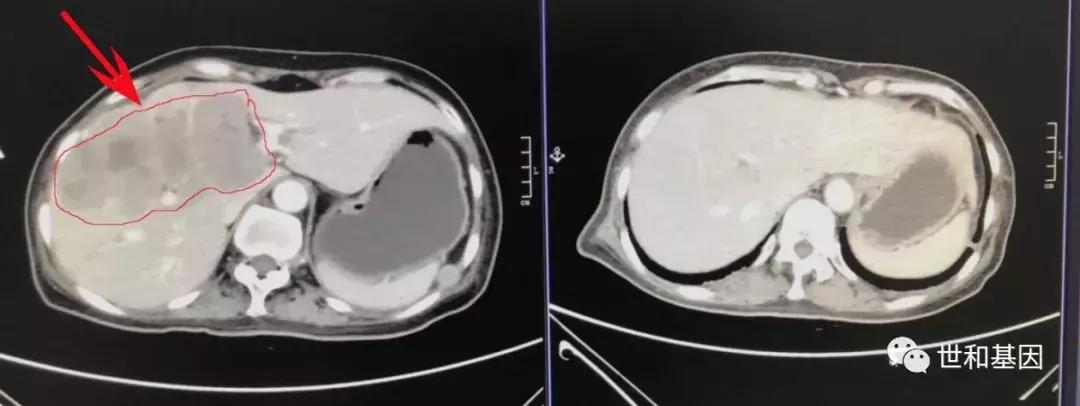

上:治疗前CT(2019-06-26)

下:治疗后CT(2019-08-13)肝脏病灶及右心房癌栓明显缩小